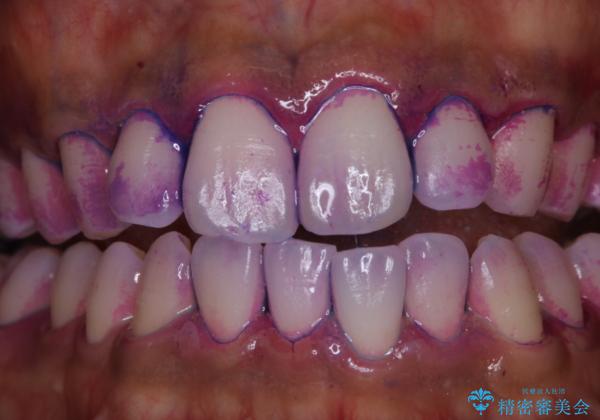

- 特に症状など気になるところはないが、メンテナンスして欲しいとのことでした。染め出しをしてのブラッシング指導とPMTC30分コースを行いました。

染め出しをすると、現在付着しているプラークを確認できて、今後の正しいハミガキの方法を知るチャンスとなります。